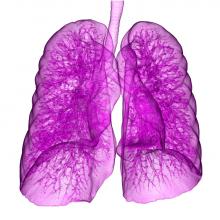

The American Society of Radiologic Technologists (ASRT) has introduced Low-Dose Computed Tomography (LDCT), an online education product designed to teach radiologic technologists LDCT screening techniques for patients with lung cancer. The module also provides guidance for radiology managers looking to provide reimbursable LDCT services to patients in the Medicare program.

Radiotherapy using protons can deliver more accurate treatment to a tumor while reducing the dose to surrounding tissue. However, in mobile organs such as the lung, precise targeting of the dose is difficult. Now researchers have succeeded in making a model of breathing movement that allows for the precise measurement of narrow beams to a dummy tumor by simulating the motion and physical properties of the chest anatomy in a model, which was presented at the 3rd European Society for Radiotherapy and Oncology (ESTRO) Forum in Barcelona, Spain.